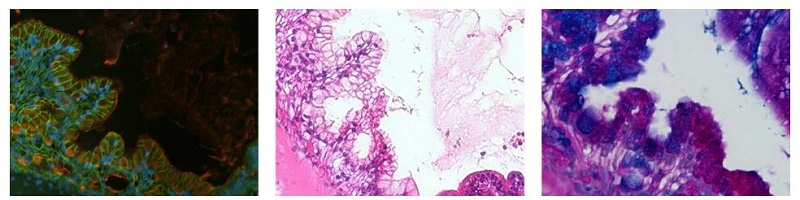

30 天以上類器官的免疫染色顯示復(fù)雜的折疊結(jié)構(gòu)、柱狀上皮、隱窩樣結(jié)構(gòu)和許多胃腸道標(biāo)志物的表達,包括前腸標(biāo)志物 PDX1、后腸標(biāo)志物 CDX1、MUC1 MUC5AC 陽性粘蛋白分泌細(xì)胞、溶菌酶 (LYSO) - 陽性潘氏細(xì)胞和絨毛蛋白 (VILL) 陽性腸細(xì)胞。類器官周圍的細(xì)胞包含異質(zhì)細(xì)胞群,這些細(xì)胞表達波形蛋白 (VIM)、纖連蛋白和平滑肌α肌動蛋白 (α-SMA)。粘蛋白表達僅限于杯狀細(xì)胞和類器官的中央腔,其中還含有死細(xì)胞和碎片H&E PAS-Alcian Blue 進行的組織學(xué)染色顯示存在酸性和中性粘蛋白,以及成熟類器官內(nèi)的組織樣形態(tài)